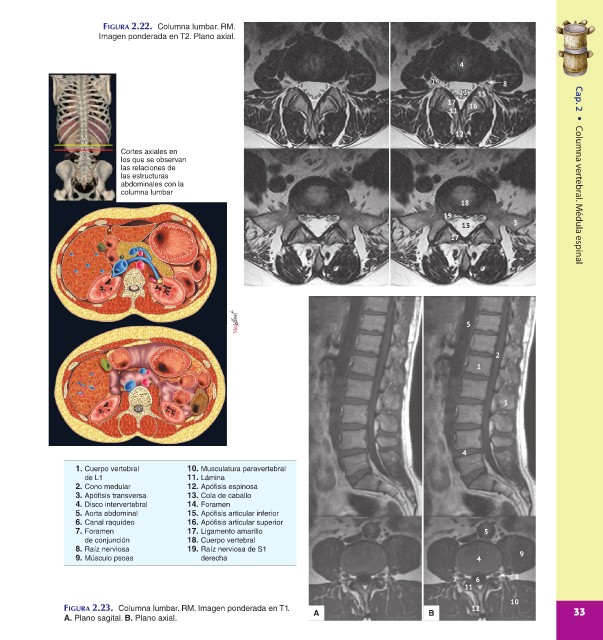

FIGURA 2.22. Columna lumbar. RM.

Imagen ponderada en T2. Plano axial.

Cortes axiales en

los que se observan

las relaciones de

las estructuras

abdominales con la

columna lumbar Columna vertebral. Médula espinal

1. Cuerpo vertebral 10. Musculatura paravertebral

de L1 11. Lámina

2. Cono medular 12. Apófisis espinosa

3. Apófisis transversa 13. Cola de caballo

4. Disco intervertebral 14. Foramen

5. Aorta abdominal 15. Apófisis articular inferior

6. Canal raquídeo 16. Apófisis articular superior

7. Foramen 17. Ligamento amarillo 5

de conjunción 18. Cuerpo vertebral

8. Raíz nerviosa 19. Raíz nerviosa de S1 9

9. Músculo psoas derecha 4

FIGURA 2.23. Columna lumbar. RM. Imagen ponderada en T1. A B 12 33

A. Plano sagital. B. Plano axial.